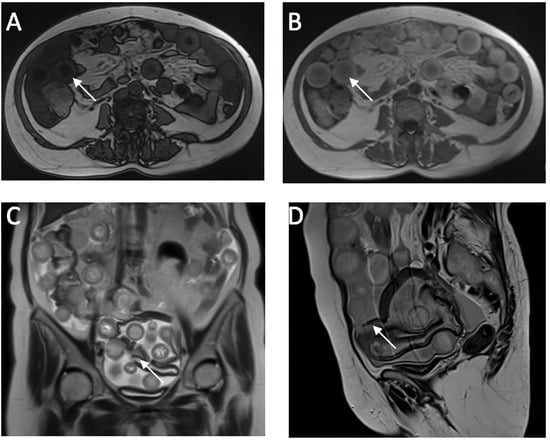

Ruptured Ovarian Cystic Teratoma: A Rare Diagnosis, Easily to Be Confused with Peritoneal Carcinomatosis

3. Case Presentation